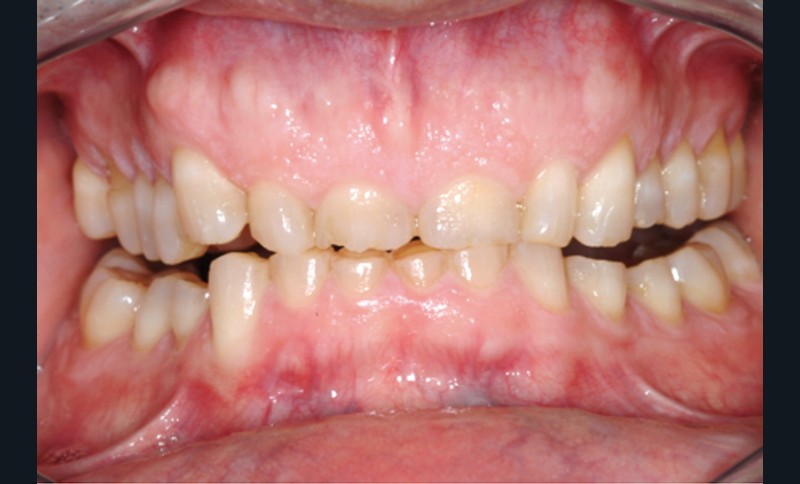

Jean-Pierre Attal : Tout à fait. Mais il faudra donner au prothésiste un maximum d’indications pour qu’il puisse réaliser sa cire de diagnostic. Vous découvrirez que la première étape de la réalisation de ces « full mock-up » est la réalisation d’un projet esthétique virtuel [8] à partir de cadrages photographiques précis aux trois échelles (visage, sourire, dento-gingivale). Gil Tirlet nous expliquera tout cela en détail avec des vidéos que j’ai déjà visionnées et qui sont très impressionnantes (fig. 1 à 4) !

Jean-Pierre Attal : Exactement, car il est possible d’appliquer le protocole de la technique « 3 steps » aux patients présentant des pertes de substance d’origine attritive (bruxisme) (fig. 5).